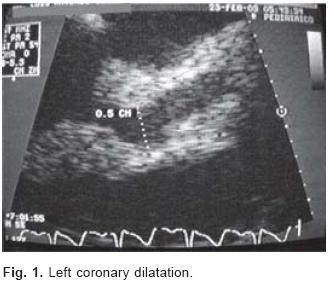

Nineteen patients accumulated globular speed, 18 presented leukocytosis con neutrophilia, 14 had thrombocytosis, Creactive protein was positive in eight, including four patients with an elevation of > 6 μgr/dL, eight patients presented moderate elevation of aspartate and alanine aminotransferases of not > 100 μ/L (these patients had negative serology for hepatitis A, B, and C), one patient had an elevation of lactic dehydrogenase and creatine phosphokinase, one with an elevation of antistreptolysines of > 500 (μ/L, and in one patient we observed an elevation of immunoglobulin E. During the study period, we carried out during the study period and on the majority of patients additional laboratory examinations including the following: febrile reactions; hemocultures; pharyngeal culture; cutaneous reactions to coccidioidomycosis and tuberculosispurified protein derivative (PPD) tuberculosis; immunoglobulins IgA, IgG, IgM, and IgE; antimycoplasma antibodies (AMA) in five patients; rheumatoid factor; antiDNA antibodies, and neutrophil anticytoplasma antibodies, with negative results (Table III). In consultory studies, five patients showed infiltrated bronchopneumonic infiltrate and we observed cardiomegalia in one. We carried out an echocardiogram in all patients; six patients showed coronary artery dilatation with variable diameter, between 4mm to 6mm, in five was located in the left coronary and one with in the right coronary, all patients began after 10 days evolution , we observed valvular alteration in four patients, two patients had aortic insufficiency, and two presented slight mitral insufficiency (Table IV) (Figs. 1 and 2).

Coronaryartery damage was found in 6 of the 20 patients; in five, this affected the left coronary artery, and in one patient there was dilatation in the right as well as in the left coronary artery. Four patients additionally presented aortic and mitral insufficiency; in two, this was associated with coronaryartery dilatation. In the remaining two patients and as a unique finding, one child manifested left ventricular dyskinesia and cardiomegalia without coronary damage. Aortic and mitral vascular damage has been reported less frequently, although this type of lesion can be expected as a consequence of cardiac value inflammation. In paediatrics areas it is very important the knowledge of the following coronary disease risk factor: Male gender, Age less than one year old, pericarditis, myocarditis, fever more than 10 days, haemoglobin less than 10 g/dL, C reactive protein more 10 mg/dL, recurrent fever.26,12,26,33,35